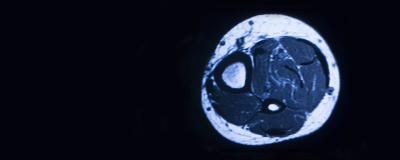

Two and half years following the initial surgery, the patient re-presented to the treating surgeon for a soft tissue mass in the volar aspect of the forearm, along the prior surgical incision site. The soft tissue mass was getting progressively larger over a span of months, with pain in the area, primarily with flexion and extension of the wrist during gymnastics. Workup of the mass was performed with magnetic resonance imaging and was unremarkable, with no identifiable muscle herniation.

Advanced imaging for muscle herniations includes ultrasound and MRI. Dynamic aspects of each of these modalities assists with identifying patients with vague or occult findings. The use of dynamic ultrasound is available and low cost, however, is user dependent. Kendi et al demonstrated dynamic MRI could also be utilized to determine size of muscle herniation and extend of the fascial defect. Interestingly, in this case, the MRI did not demonstrate a muscle herniation in our patient; however, it was apparent intraoperatively the herniation occurred in pronation and resolved in supination. This clinical scenario emphasizes the value a dynamic MRI contributes as it is not uncommon for these herniations to occur only with contraction of the affected muscle belly.